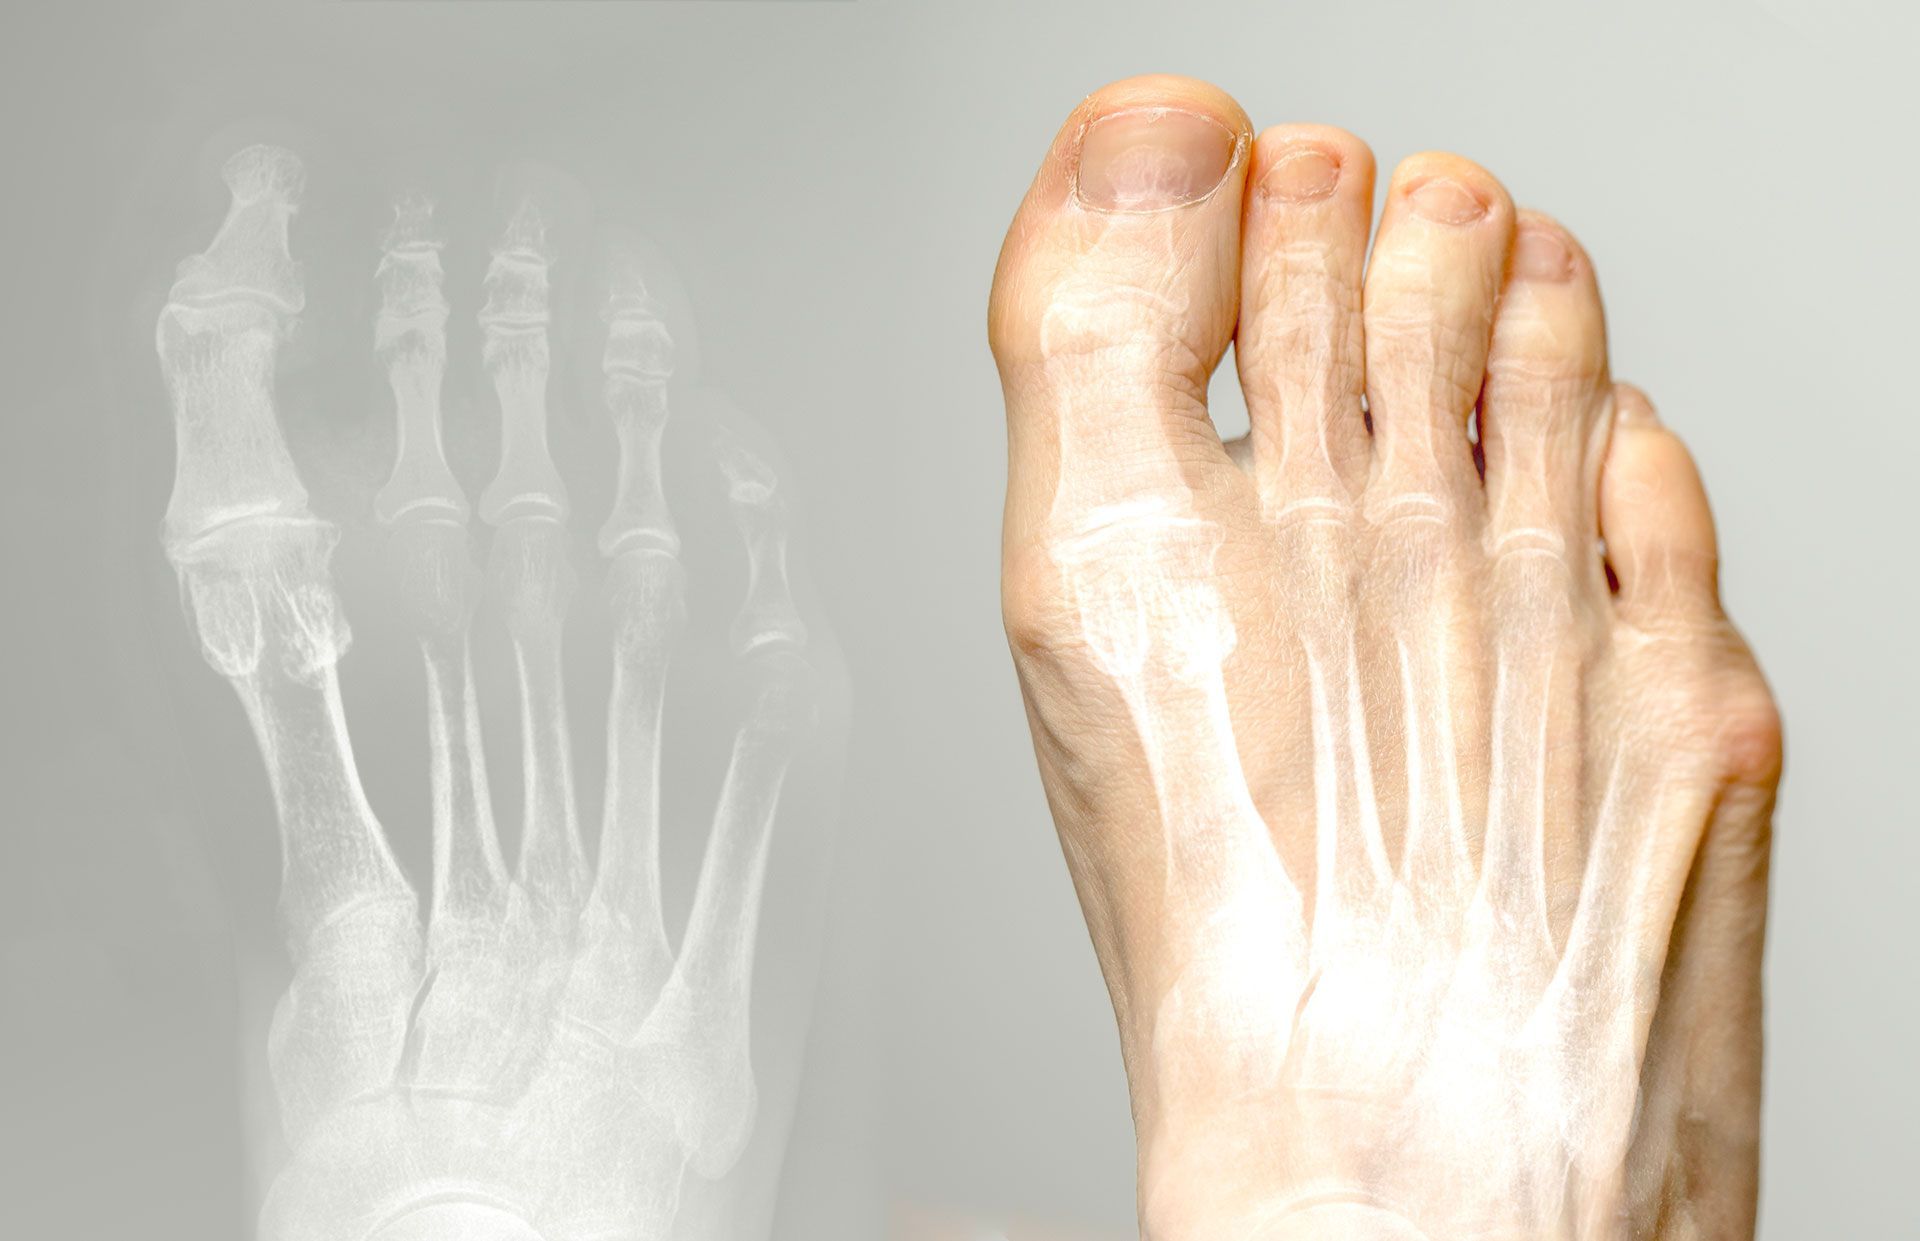

Hallux rigidus is a degenerative arthritis condition affecting the big toe joint that causes progressive stiffness, pain, and limited range of motion, making walking, running, and even wearing certain shoes increasingly difficult if left untreated.

Our comprehensive hallux rigidus treatment program offers multiple proven management methods to effectively reduce pain and restore function to your big toe joint. We provide thorough evaluations using physical examination, range of motion assessment, and diagnostic imaging to determine the stage of arthritis and extent of joint damage, then develop personalized treatment plans that may include custom orthotics with Morton's extensions, rocker-bottom shoe modifications, anti-inflammatory medications, corticosteroid injections, physical therapy for joint mobilization, activity modification guidance, and surgical options such as cheilectomy (bone spur removal), joint fusion, or joint replacement for advanced cases depending on the severity of your condition and lifestyle requirements.